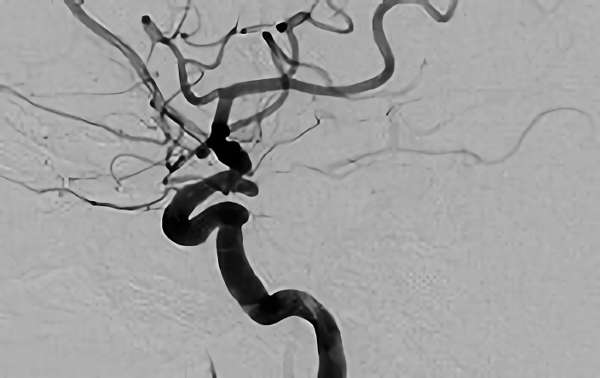

No.1631 手術後